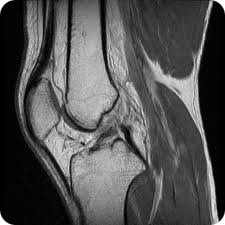

Knee icon Atlas: Knee

Lecture: Meniscus

Lecture: Patellar Measurements

Cases: Basics J. Harter

Cases: Lateral corner S. Honowitz

Cases: Medial corner S. Honowitz

Knee illustration illustration by Kate Stevens MD